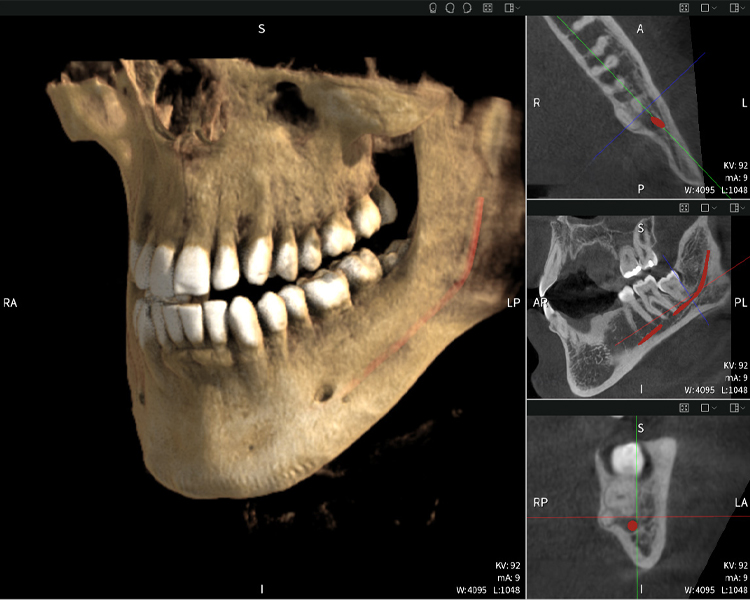

Figura d: Resultados de imagen de Seethrough Max, sobre un fondo negro.

Figura d

Las figuras b–d muestran varias vistas de una reconstrucción 3D de la mandíbula, proporcionando una visión general completa de la anatomía mandibular, la posición de los nervios en relación con los dientes y permitiendo evaluar la simetría y alineación dentaria.